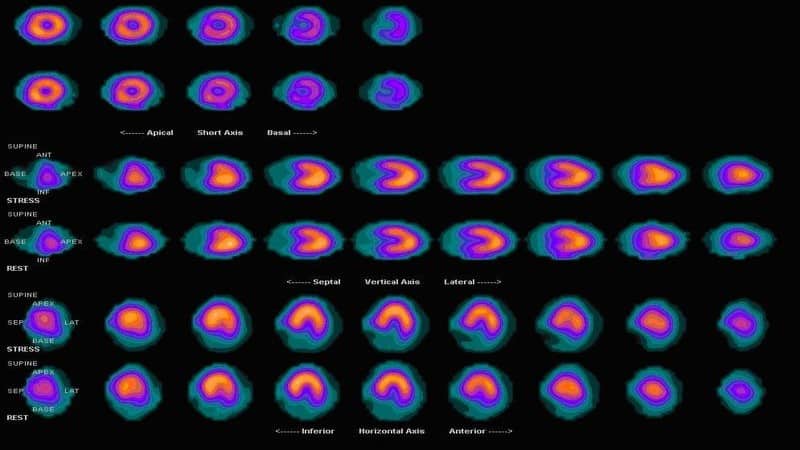

Myocardial Perfusion SPECT: Background, Indications, Contraindications Interpretation of SPECT/ CT Myocardial Perfusion Images: Common Arti- facts and Quality Control Techniques1 Heart attack, SPECT scan - Stock Image - C013/1043 - Science Photo Library Spect Scan Heart